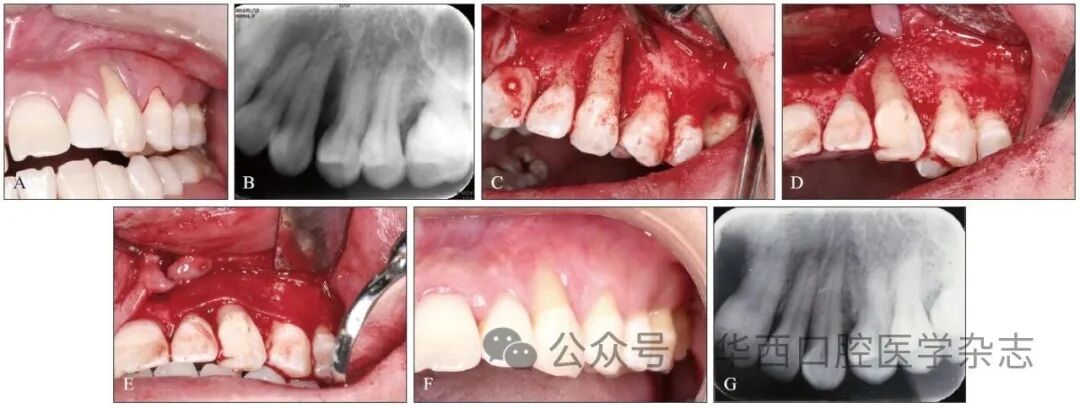

笔者也在保存重度牙周炎患牙方面努力尝试,下面这个年轻患者的左侧上颌尖牙病损严重,但该牙的存留对于整体咬合功能和面形均有较大影响,在征得患者知情同意后,实施了再生性手术治疗,不仅保存住患牙,也为后期软组织美学修复创造了机会和更可靠的条件(图4)。

▲图 423牙唇侧及邻面重度骨吸收及附着丧失,行植骨联合GTR术保存治疗▲Fig 4Severe bone resorption and attachment loss on the labial and adjacent surfaces of tooth 23, which was preserved by bone grafting combined with GTR techniqueA:术前口内照;B:术前X线片;C:术中骨缺损;D:植骨;E:覆盖胶原膜;F:术后3个月口内照;G:术后3个月X线片。